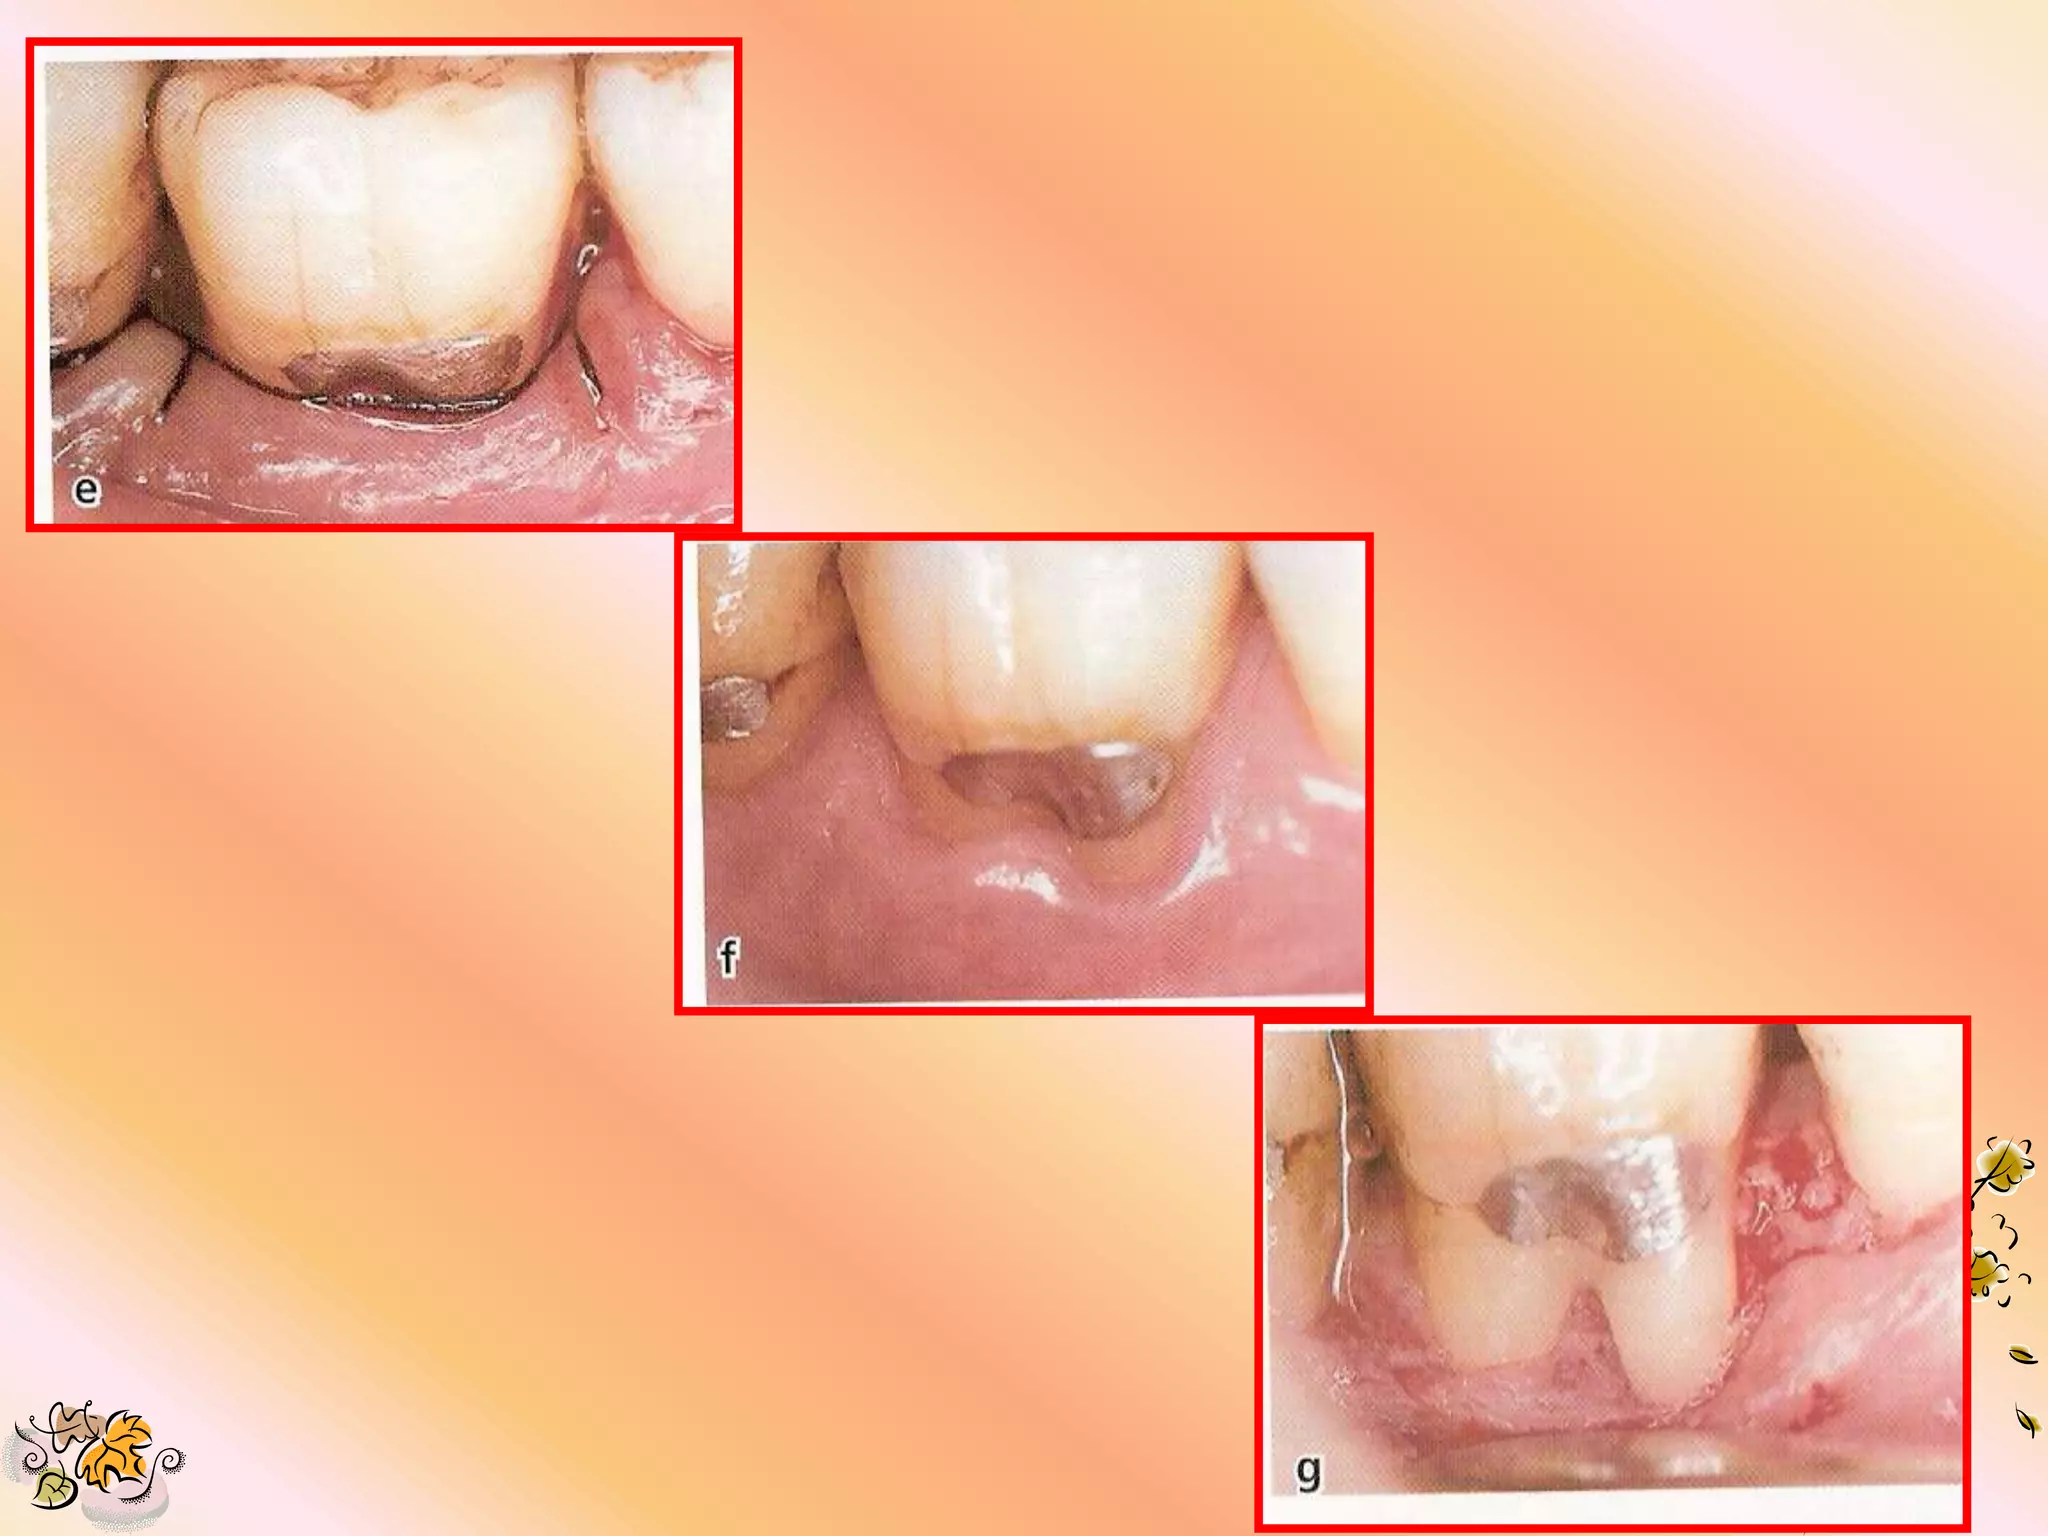

SUTURING TECHNIQUES 1. Sling suture are used to approximate material over the defect without engaging the flap or tissue. 2. The material must fit tightly against the tooth surface at all points to prevent epithelial proliferation b/w tooth & material & to help in stabilizing the wound.

3. The flapmargin should ideally be 2 to 3 mm coronal to the material. 4. Tight flap apposition is desired to avoid premature flap opening & material exposure.

MATERIAL REMOVAL 1. Removalshould be 4 to 8 wks after placement or any time a serious complication occurs.

2. If thematerial can not be removed with a gentle tug, sharp dissection is recommended.

3. Extreme careshould be used to avoid damaging the underlying the new granulation tissue. 4. A small tissue forcep is used to remove the material. 5. The flap is re-approximated over the new tissue & sutured with silk suture.